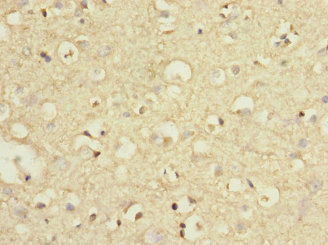

圖片:

應用范圍:ELISA, IHC

Application Recommended Dilution IHC 1:20-1:200 -

組織特異性:Expressed in many areas of the brain, especially in the cerebral cortex, hippocampus, and cerebellum. Expression of GRM7 isoforms in non-neuronal tissues appears to be restricted to isoform 3 and isoform 4.